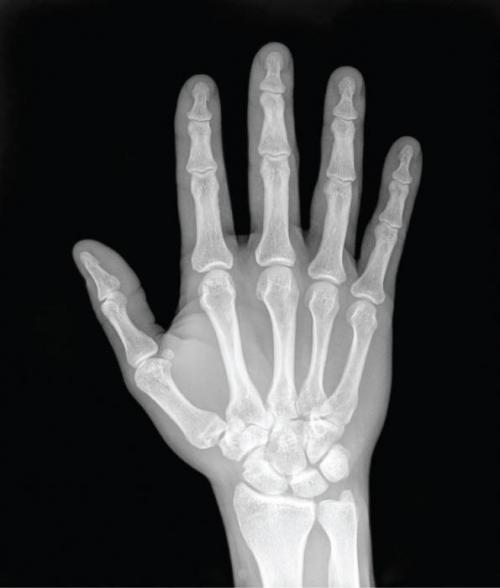

Верхняя конечность условно делится на плечо, предплечье и кисть. Последняя имеет особенную анатомию, поскольку включает 27 отдельных костей, соединяющихся между собой суставами, что укрепляются связками, мышцами и сухожилиями. В кисти выделяют запястье, кости пясти и фаланги пальцев. Такое деление связано с анатомией этого участка опорно-двигательного аппарата, но функционирование происходит совместно.

Кисть руки в дистальном участке заканчивается пальцами, структурные компоненты которых называются фалангами. На мизинце, среднем и указательном пальце число фаланг равно 3, на большом — 2. Они состоят из головки, тела и основания. Строение каждого из пальцев рук отличается лишь размерами и объемом, что индивидуально для конкретного человека.

Врач на приеме быстро определит, что случилось - ушиб или перелом. Для точного диагноза нужно посетить хирурга. После общего осмотра доктор направляет на рентген, который выполняется с двух сторон. На снимке будет виден сам перелом и, если имеются, смещения - раздробленность. После получения снимка врач назначит дальнейшее лечение.

Но бывают тяжелые случаи, при которых и со снимком картина не становится ясной. В таких ситуациях помогает компьютерная томография. С помощью современной диагностики можно увидеть перелом и разорванные связки.

Итак, разберемся в том, сколько костей на руке у человека, а именно на ее запястной части. В этом месте находятся восемь костей, которые располагаются в два ряда (проксимальный и дистальный). Кроме этого, каждый отдельно взятый палец состоит ровно из 3-х фаланг. Исключение составляет лишь большой, в котором их всего лишь две. После кисти рука состоит из локтевой и лучевой косточек, а также плечевой кости, предплечья, ключицы и лопатки. Таким образом, ответом на вопрос о том, сколько костей на руке, является вышеупомянутая цифра 32.

Анатомия кисти руки человека — объемный комплексный раздел, который включает в себя скелет и устройство отделов кисти . Кисть руки состоит из 27 мелких косточек, которые распределяют на себе остальные ткани — связки, мышцы и кожу, обеспечивают кисти гибкость.

Скелет кисти руки (на латыни manus) поделен на три отдела — запястье, пясть и фаланги пальцев . Подробно рассмотрим сколько костей в кисти и сколько фаланг на большом пальце.